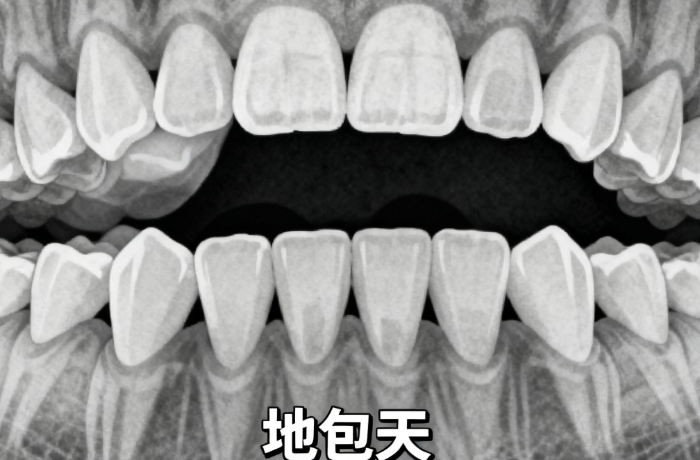

8. 隱適美復(fù)雜款:36800元/全口(含個性化矯治器+拔牙優(yōu)惠+牙周護理,適配深覆合、地包天等復(fù)雜情況);